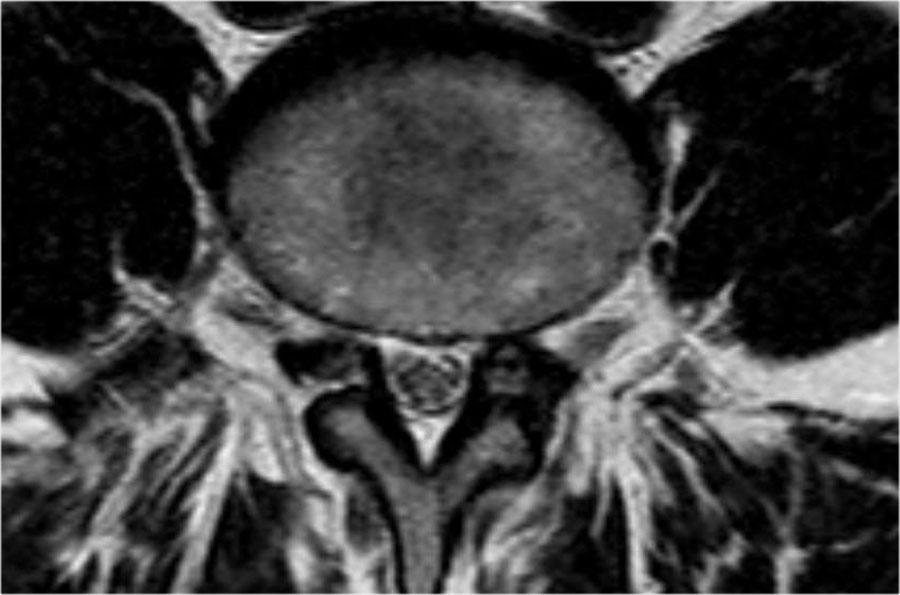

Cường độ tín hiệu của thoát vị đĩa đệm trên chuỗi xung T1W thường ở mức trung gian, trong khi trên chuỗi xung T2W có thể tăng tín hiệu trong trường hợp nhân nhầy thoát vị mới hoặc giảm tín hiệu trong trường hợp thoát vị cũ hơn.

Hình ảnh thoát vị tăng tín hiệu (mũi tên vàng trên ảnh cắt ngang) trượt qua vết rách vòng sợi và chèn ép rễ thần kinh L5 bên trái (mũi tên xanh dương).